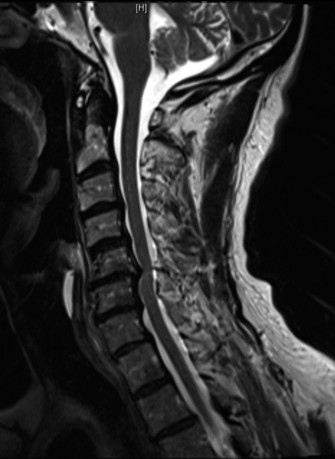

Recognize surgical and nonsurgical indications for a thoracic lymphoma? Definitively manage a thoracic lymphoma? CASE 13 A 23-year-old man was involved in a high-speed motor vehicle accident. On presentation to the trauma bay, his chief complaint was neck pain. Physical examination demonstrated that he was neurologically intact. Images of the cervical spine are shown in Figure 1–19A–B. Full workup demonstrated no other injuries.

Figure 1–19 A–B

The correct answer is (B). The imaging clearly demonstrates a Hangman’s fracture, also known as a C2 traumatic spondylolisthesis. The hallmark of this injury is a fracture through the pars interarticularis of C2, which effectively dissociates the anterior elements from the posterior arch and facet joints. A Jefferson fracture refers to C1 ring fractures that can have varying degrees of lateral displacement. There is no evidence of vertebral body comminution with posterior vertebral body involvement, which would be characteristic of a burst fracture. While some Hangman’s fractures can be associated with facet dislocation, there is no evidence of this on the imaging.

The correct answer is (B). Type I fractures have minimal horizontal displacement, no angulation, and the C2–3 disc remains intact. Type II fractures are both displaced and angulated, presumably hinging around the anterior longitudinal ligament. Importantly, these fractures reduce with longitudinal traction. Type IIA fractures have minimal horizontal displacement but are significantly angulated. It is presumed that the anterior fragment rotates in place, most likely disrupting the anterior longitudinal ligament. These injuries are worsened by traction and reduced with axial compression. Type III fractures have bilateral C2–3 facet dislocations.

The correct answer is (B). While type I fractures can be treated immediately in a hard collar, type II fractures are best treated initially with traction to achieve fracture reduction. After a short period of traction, the patient should be placed in a halo vest to allow mobilization. As indicated above, type IIA fractures should not be placed in traction; patients should be placed in a halo vest with some axial compression applied. Type III fractures require surgical reduction of the facet dislocation and internal stabilization. Objectives: Did you learn...? Identify a Hangman’s fracture based on imaging? Understand the classification of Hangman’s fractures?